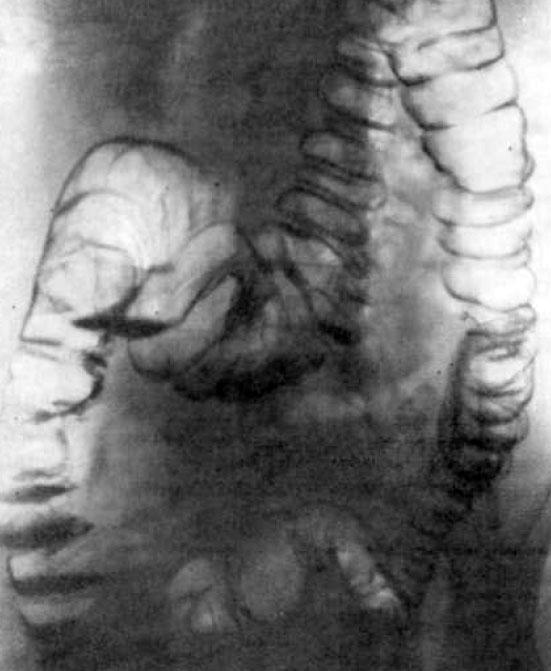

Анатомические и функциональные особенности толстого кишечника визуализируются его при контрастной ирригоскопии. Колоноскопия позволяет досконально изучить состояние слизистой на всем протяжении толстой кишки. Кроме того, проведение колоноскопии позволяет взять биоптаты слизистой кишечной стенки для дальнейшего гистологического исследования.